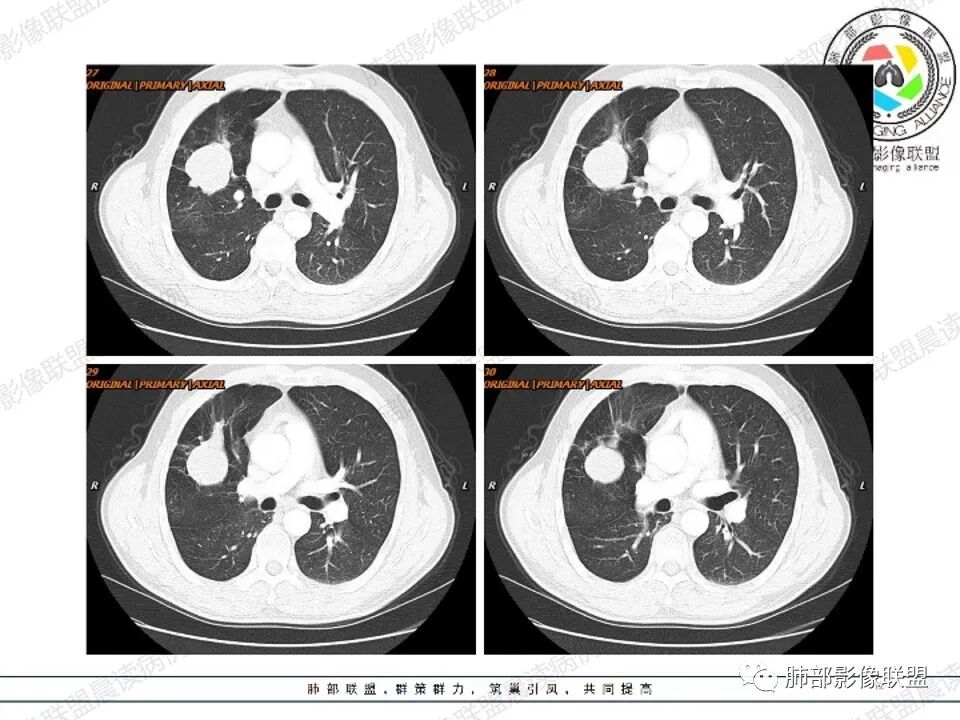

病例二

左肺下叶肿块影平行支气管生长,边缘有纤维索条影,整体边缘平直,略彭隆,边界清楚,伴行支气管堵塞,周围伴有肺气肿,增强扫描强化不明显,无明显实性病变,考虑良性,支气管闭塞?支气管囊肿?平滑肌瘤。

左肺下叶孤立性肿块,形态规则,密度均匀,边界清,周围可以气肿及条索,无强化,左肺下叶后基底段支气管未见发育?考虑发育畸形,支气管囊肿 ?闭锁?先天性囊性腺瘤样畸形?

老年女性,查体发现,左肺下叶不规则实性肿块,边缘平直收缩,无毛刺,周围有纤维牵拉及肺气肿,强化不明显。先天肺发育不良,支气管闭锁。

左肺下叶扁平形结节,边缘光滑平直,边界清晰,周围肺气肿,强化不明显,支持先天肺发育不良,支气管囊肿

左肺下叶不规则高密度早灶,边缘平直为主,界清,周围有肺气肿,无强化,考虑良性病变,支持先天肺发育异常,支气管闭锁,鉴别支气管囊肿,囊腺瘤样畸形。

左肺下叶高密度,边缘光滑,周围肺气肿,强化不明显,ccam?鉴别 隔离

左肺下叶肿块,边缘光滑,支气管动脉伴行,周围肺气肿,考虑支气管闭锁